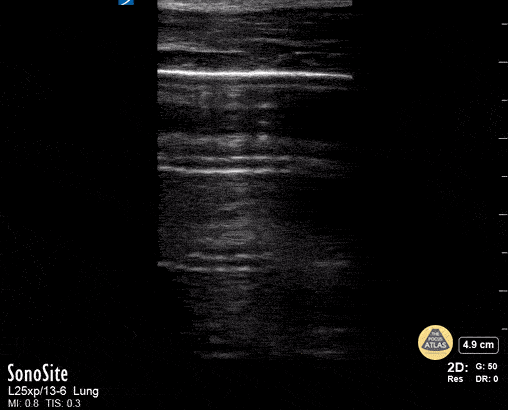

Peds-Lung - Normal Lung Slide

Normal lung sliding using linear probe Contributor: Peter Gutierrez, MD, FAAP, Emory University School of Medicine/Children's Healthcare of Atlanta, @pocuspete